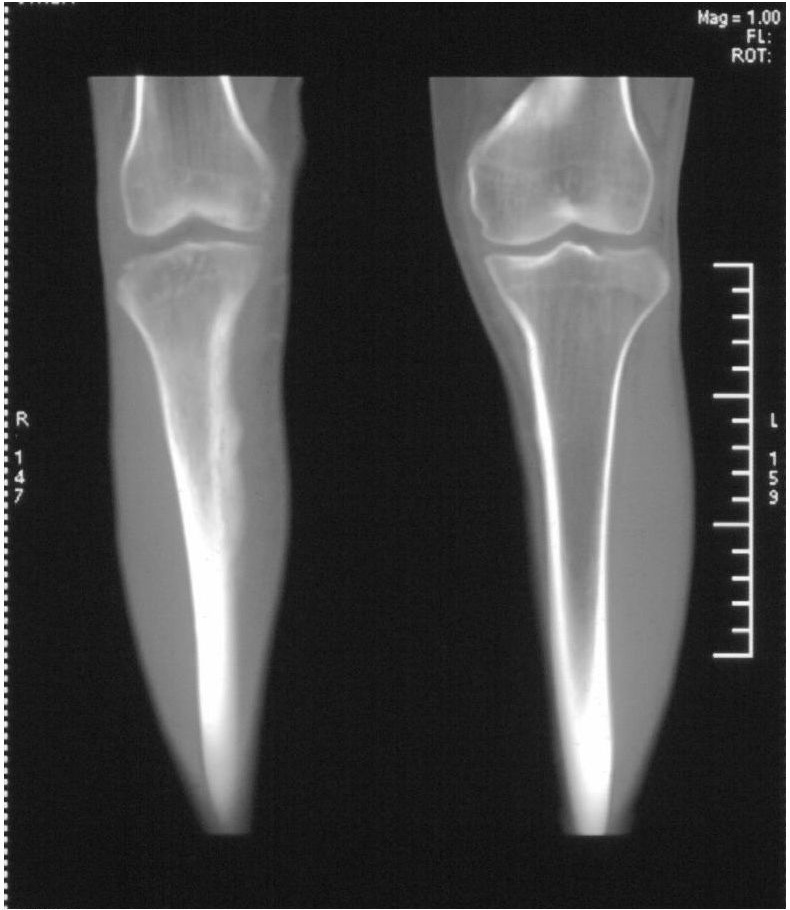

髓腔密度呈絮状增高,胫骨上端内侧可见层状骨膜反应,考虑骨髓炎.

髓腔密度呈絮状增高,胫骨上端内侧可见层状骨膜反应,肌间隙模糊,考虑骨髓炎.